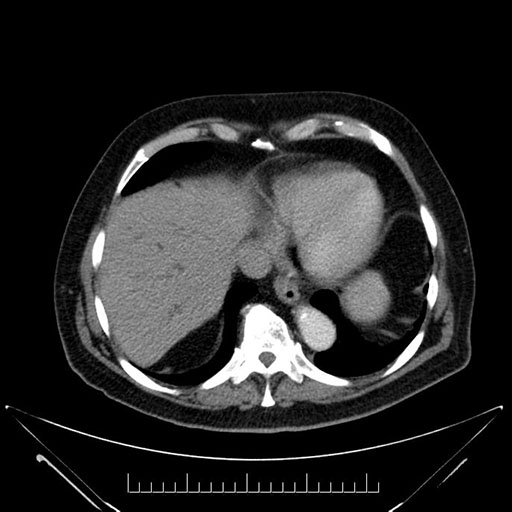

Imaging Analysis

Look through the patient's CT scan to identify any areas of concern for the necessary procedure.

Based on your CT findings, which issue(s) would give reason for "planned slowing down moment(s)" in this case?